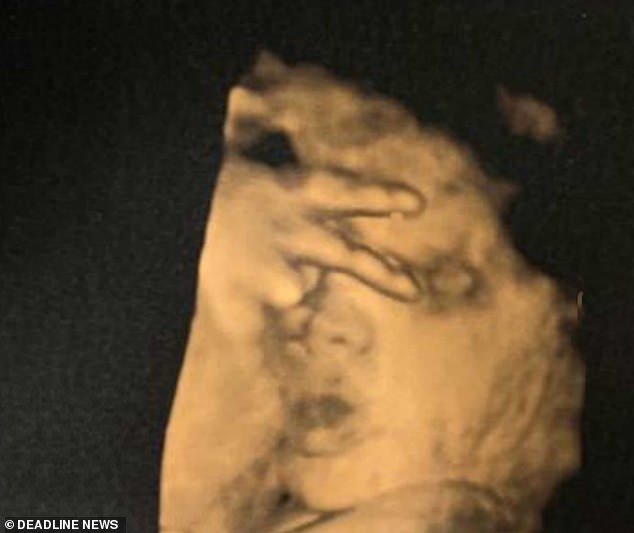

Ende në barkun e nënës, foshnja ngre dy gishtat para “kamerës”

BRITANI E MADHE- Një foshnje ende e palindur është fiksuar teksa ngrinte dy gishtat, ndërkohë që nëna e saj po bënte ekon për kontroll.